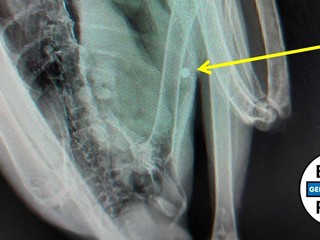

Il rapace è stato colpito all’addome e a un’ala da colpi di fucile, come i volontari hanno scoperto dopo aver eseguito le radiografie. “Per quest'aquila si prospetta un lungo periodo di degenza - spiegano da ENPA -.

Abbiamo già pianificato un intervento di osteosintesi per ridurre la frattura e mettere in asse l'osso. L'obiettivo è farla volare di nuovo alla faccia di chi, evidentemente frustrato e insoddisfatto da una vita povera di bellezza e di valori, non sa fare niente di meglio che alzare un fucile e sparare. Forse l'invidia per cotanta bellezza, forse semplicemente il desiderio di togliere di mezzo un "fastidio" e poter sparare in santa pace alle proprie "prede", forse semplicemente cattiveria.